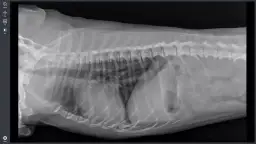

- Badania diagnostyczne (np. USG, RTG) - 200-600 zł

Podczas wizyty u weterynarza mogą pojawić się dodatkowe koszty, które nie są związane z podstawową konsultacją. Na przykład, jeśli weterynarz zaleci wykonanie badań diagnostycznych, takich jak badania krwi czy prześwietlenie, mogą one wiązać się z dodatkowymi wydatkami. Koszty tych usług mogą się znacznie różnić w zależności od kliniki oraz lokalizacji.